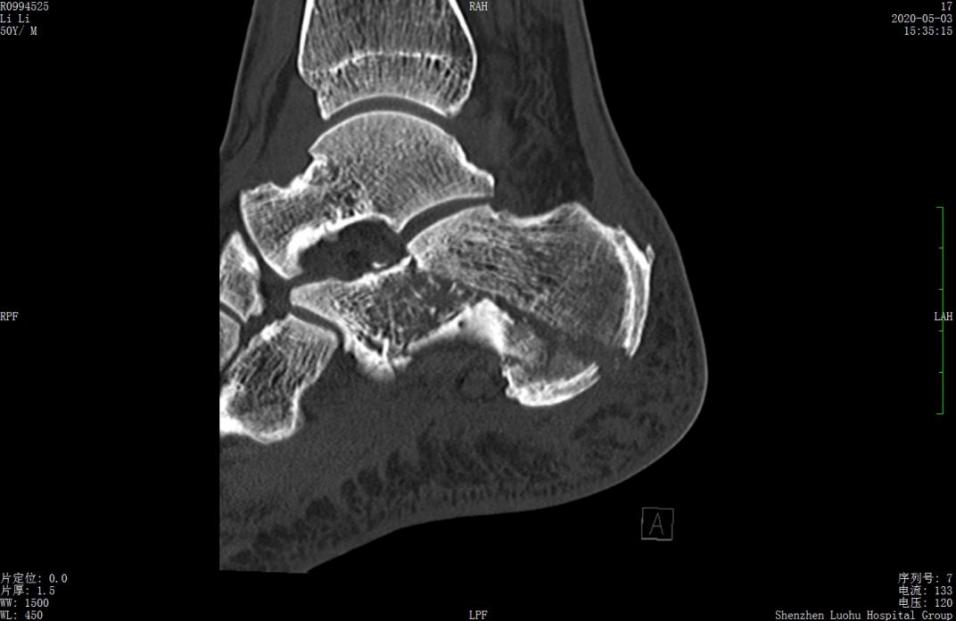

案例2影像

术前CT示跟骨粉碎骨折